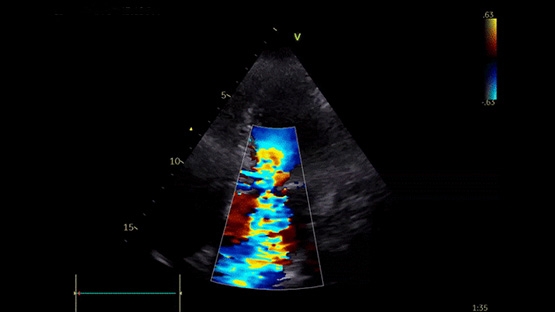

Établir le diagnostic complet d’amylose cardiaque